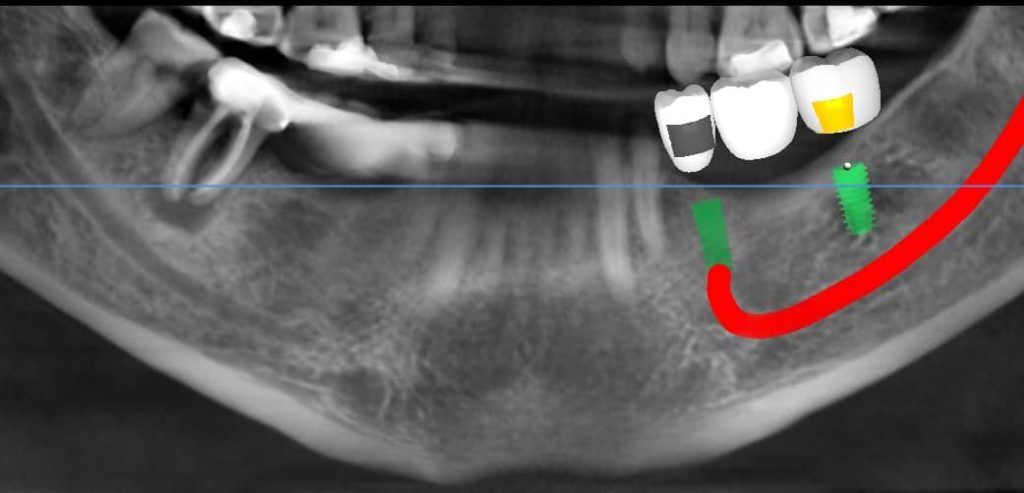

تصویربرداری سه بعدی( CBCT):

اسکن سه بعدی فک و دندان ها انجام میشود تا ساختارهای دقیق استخوان و موقعیت عصب ها مشخص شود

طراحی دیجیتال:

با استفاده از نرمافزارهای پیشرفته، محل قرارگیری دقیق ایمپلنت طراحی و شبیه سازی میشود

ساخت راهنمای جراحی( Guide surgical):

با پرینتر سه بعدی ابزار خاصی تولید میشود که به جراح کمک میکند ایمپلنت را با دقت بسیار بالا در جایگاه مناسب قرار دهد